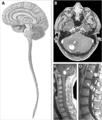

The occurrence of intramedullary tumors is relatively rare, but their treatment is often very demanding. Approximately 90% of all intramedullary spinal tumors are glial tumors, the most common of which are ependymomas (60%) and astrocytomas (30%). The third place is represented by hemangioblastomas. These neoplasias are primarily treated surgically, but there is often no possibility of complete resection due to the eloquent location and size of the tumors. Surgery and radiosurgery / chemotherapy are usually added. [4][28] náhled|MRI – spinální myxopapilární ependymom

Spinal cord ependymomas are more common in adult patients (typically between 35 and 45 years of age) and represent the majority (60%) of all primary intramedullary tumors. [4][45][46]. There are both benign, semi-minimal and malignant forms [47]. Most often, spinal ependymomas are located in the thoracic segment of the spinal cord, although they can occur along its entire length. [4].